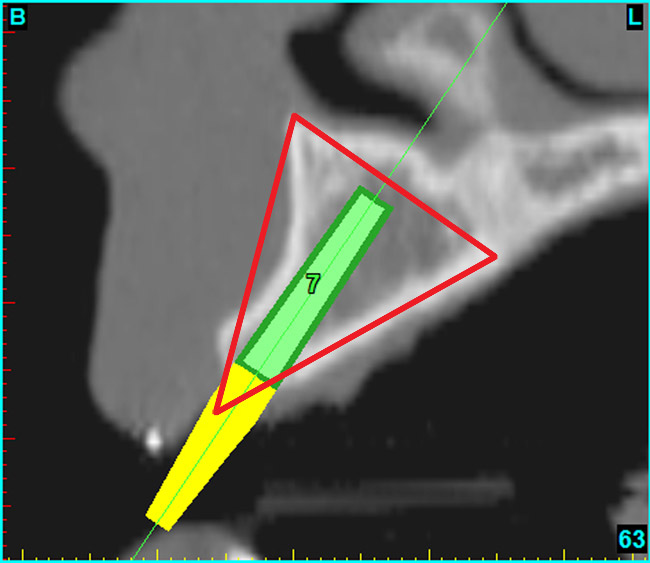

Using the interactive treatment-planning software application, the scan data was assimilated and both potential lateral incisor implant receptor sites were evaluated. It is a.combination of the data and the methodology used to interpret the data that is the basis for defining a new paradigm in diagnosis and treatment planning. Proper evaluation of these images and correct use of the interactive treatment-planning software tools is essential in creating a decision tree of treatment options. First, the data from the scan was reformatted into panoramic, axial, and cross-sectional images. The undistorted cross-sectional images revealed the residual alveolar bone in the area of the right lateral incisor. Then, a simulated schematic implant was placed within the bone with an abutment extension to help visualize the connection to the restorative position of the tooth (Figure 4A). The Triangle of Bone® (TOB), a concept developed by the author to analyze bone quality, quantity, and disposition at prospective dental implant sites using CBCT scans, aided in determining available bone volume by defining a “zone” for proper implant placement18,19 (Figure 4B).

After reviewing the CT data and the decision tree, the bone within the “zone” of the TOB was evaluated and found to be satisfactory for implant placement. Because the goal of implant dentistry is not the implant but the tooth that is placed, true restorative-driven implant dentistry must begin with the assumption that the implant position should remain consistent with the tooth it is replacing, and the final implant-supported restoration.12,22-26 The TOB aids the clinician in understanding the link between the implant position and the desired restorative goal. The base of the geometric shaped “zone” is visualized by starting at the widest area of alveolar bone facially and superiorly. The apex of the triangle is positioned to bisect the alveolar crest (Figure 4B). The TOB, the overlay in the cross-sectional image, reveals whether adequate bone is available for implant placement. It also helps to identify concave facial bone defects, and accurately determine the width of bone at the crest. The author r.commends using an interactive software application that provides the necessary measurement tools to accurately assess the bone anatomy.

Figure 4b  CT scan data was input into the treatment-planning software, which allowed (A) placement of a simulated implant and (B) the determination of the “zone” for proper placement.

Figure 4b